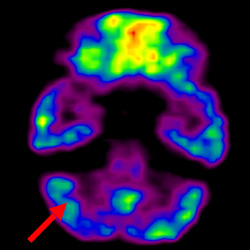

干細(xì)胞治療腦癱后改善的客觀放射學(xué)證據(jù)

細(xì)胞治療前 PET CT 掃描顯示神經(jīng)組織中的藍(lán)/黑色區(qū)域,表明腦癱引起的大腦損傷。

細(xì)胞治療后,藍(lán)色和黑色區(qū)域減少,并且看到更活躍的區(qū)域。這表明損傷減少并改善了大腦功能。

這證明細(xì)胞療法是治療腦癱兒童安全有效的方法。細(xì)胞療法可以更新大腦損傷的核心,并且可以通過 PET CT 掃描來監(jiān)測(cè)大腦的改善情況。這些細(xì)胞療法與標(biāo)準(zhǔn)治療一起促進(jìn)腦癱兒童的生長(zhǎng)和改善。